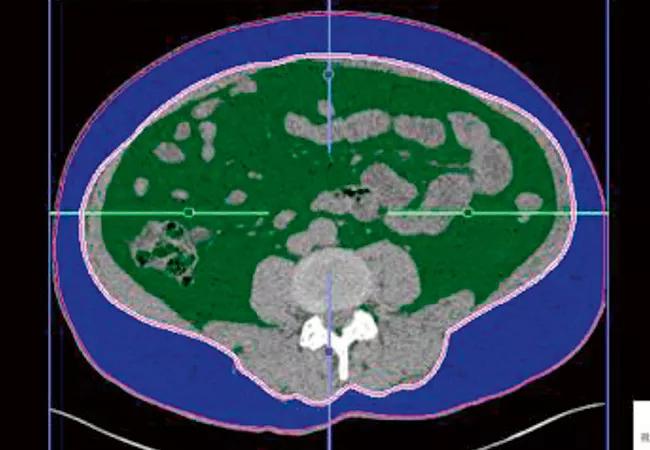

Noncontrast CT scans of kidney stones

Figure 1. Visceral fat area (VFA) shown in green; subcutaneous fat area in blue. This CT scan shows VFA was 50.4 percent.